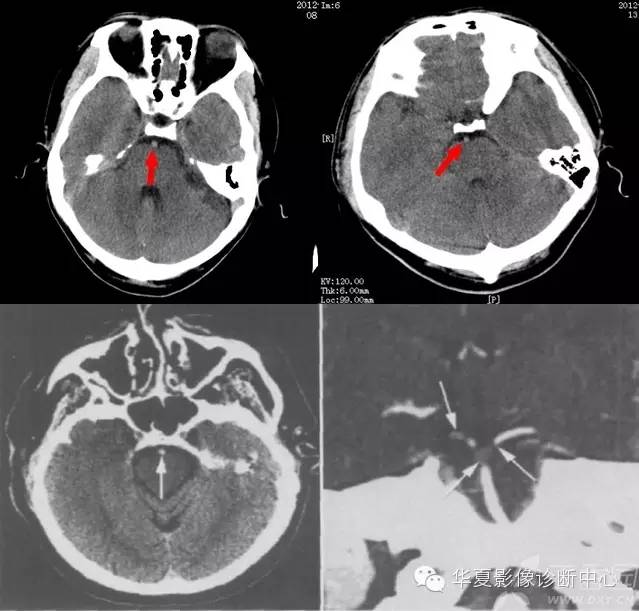

脑血管高密度征

此征可出现在颅内任何动脉、甚至静脉,是CT平扫动脉闭塞的早期直接征象,代表血栓形成或栓塞,对脑梗死的早期诊断和指导治疗有一定的意义。脑动脉高密度征最常见的为大脑中动脉高密度征(HMCAS),其次是基底动脉高密度征(HBAS)。这是因为大脑中动脉(MCA)血栓形成或栓塞引起的脑梗死最常见,占脑梗死的一半左右。另外这些动脉走行区有脑脊液,增强了组织间对比。应该指出脑动脉局部、非对称性高密度是早期脑梗死的可靠征象,若两侧动脉对称性密度增加,血栓栓塞的可能性小。HMCAS脑梗死多呈非对称性高密度征,多发生在MCA第1段和第2段,发生在第2段呈“圆点征”或“破折号征”。

上二图示基底动脉中心点征,后临床均证实为基底动脉栓塞。下左图平扫示基底动脉呈圆点状高密度(箭);右下图示 CTA示基底动脉两侧大脑后动脉起始段充盈缺损(箭)。